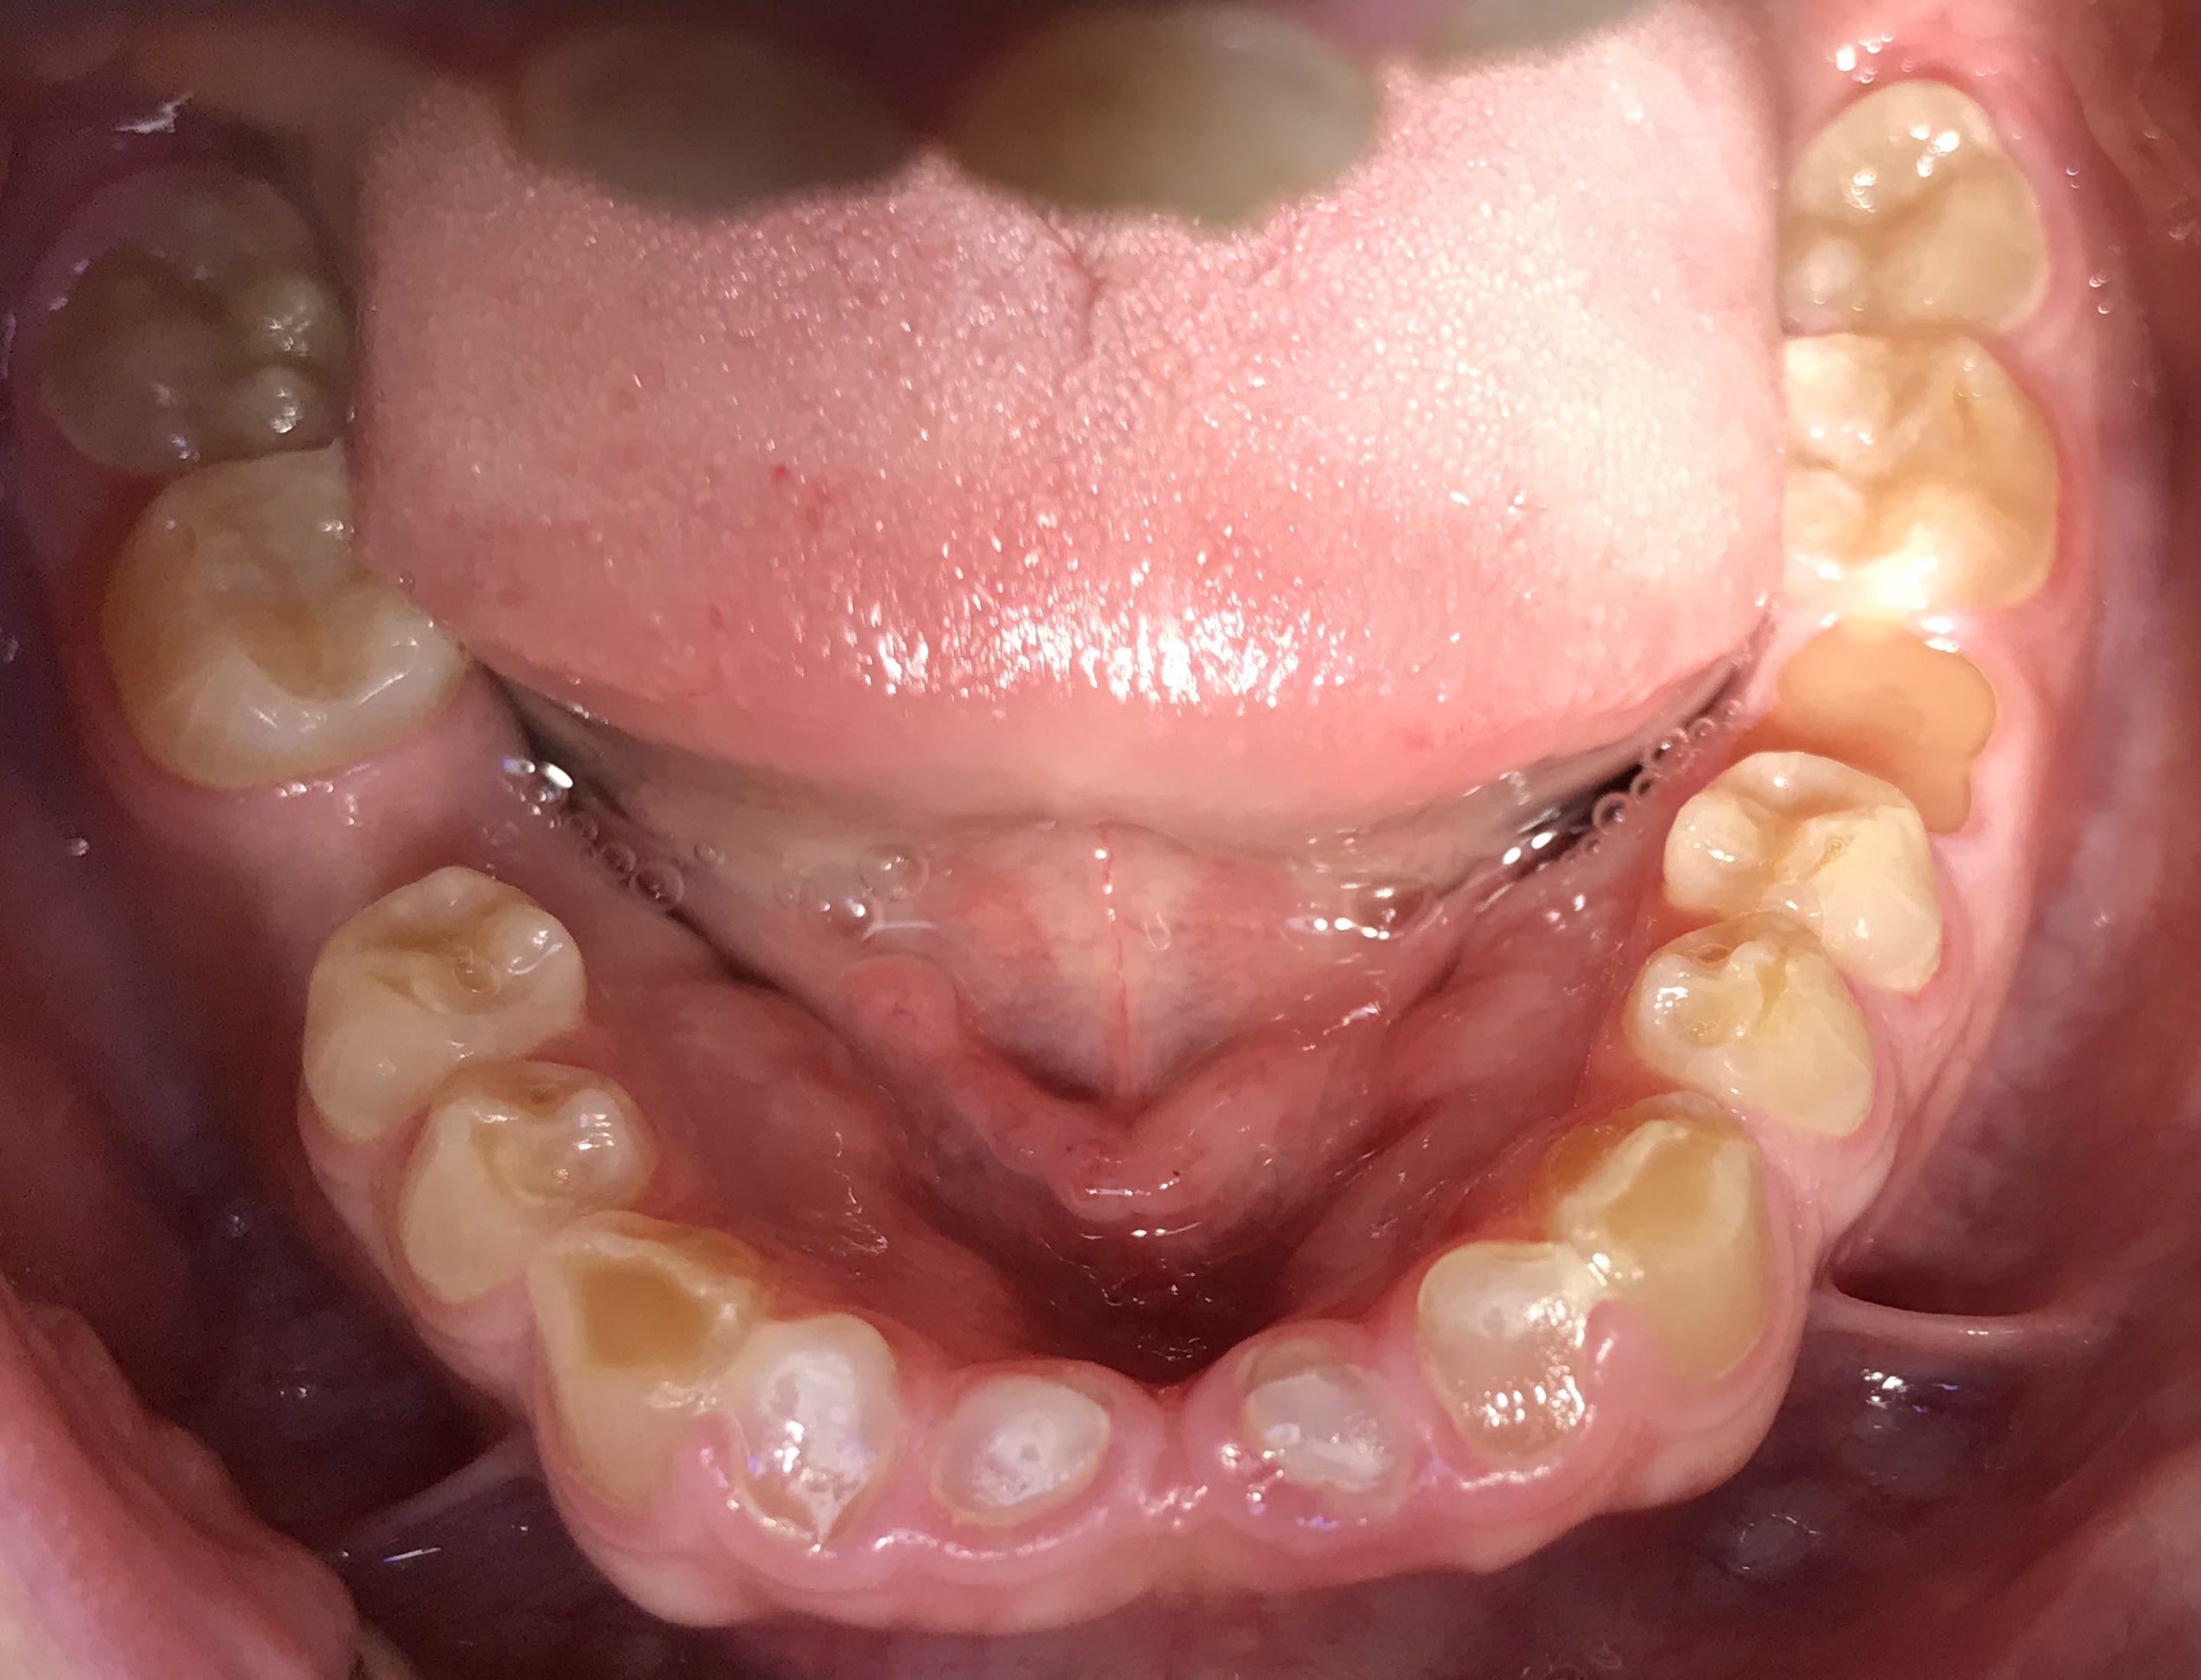

Photos

A82f03fd 2d91 4ef1 97ca f3eb47c7b10d m438gf - Eugenol

780581f7 855e 4bfa 8613 66d779c84307 rrwohx - Eugenol